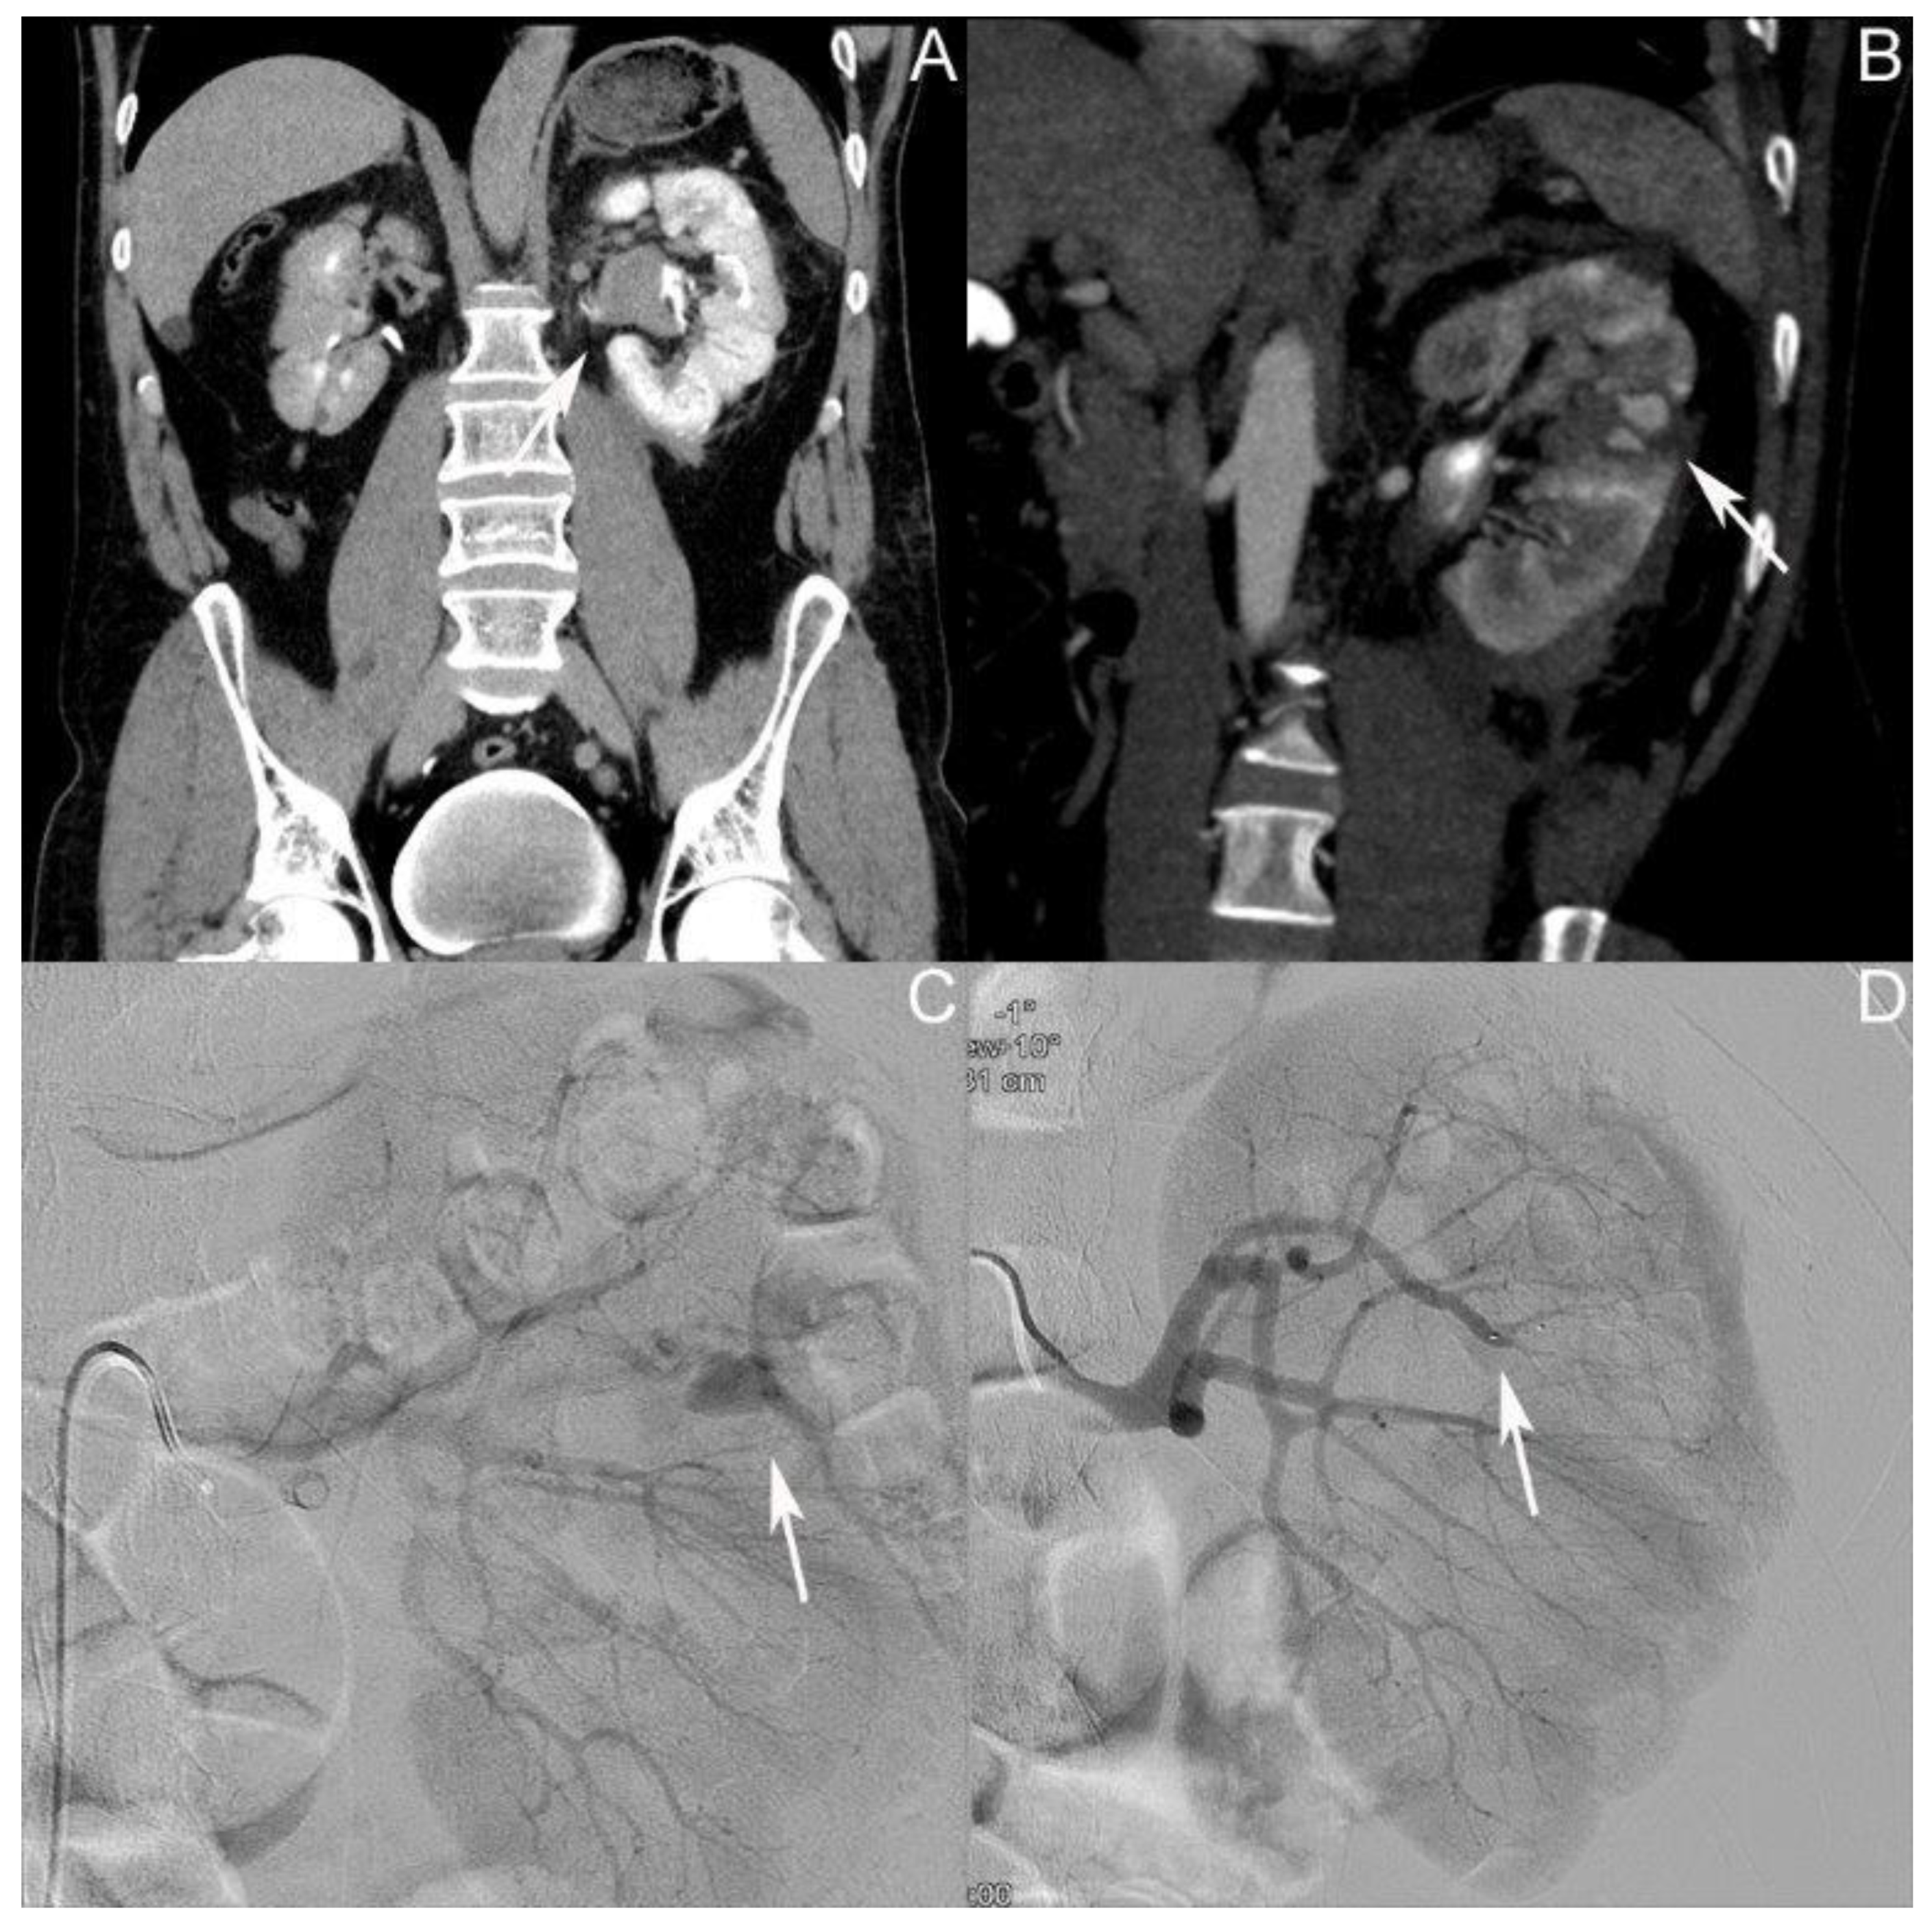

3.3. Patient III: Female Patient, Aged 56 Years

| Time of first diagnosis of AV fistula after the initial trauma in days | 13 | 1 | 7 | 7 |

| Size of AV fistula in mm | 24 | 12 | 20 | 18.7 |

| Time between trauma and onset of symptoms in days | 13 | 9 | NA | 11 |

| Number of coil embolizations performed | 2 | 1 | 2 | 1.7 |

| Time of DMSA renal scintigraphy after the trauma in days | 248 | NA | 106 | 177 |

| Result of DMSA renal scintigraphy | -No TA in the lower kidney pole on the left side -Contribution: right/left kidney 65%:35% | NA | -No TA in the lower kidney pole on the right side -Contribution: left/right kidney 61%:39% |